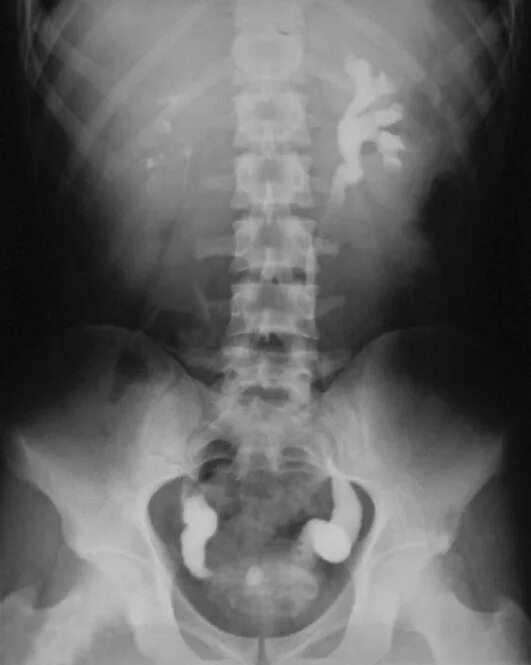

Урография с контрастом